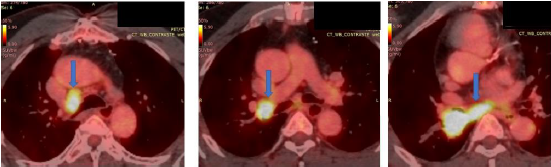

Idoso de 62 anos, com antecedentes de neoplasia de orofaringe (carcinoma de células escamosas), em 2015, tratado com radioterapia, realizou transplante hepático, em 2019, por cirrose hepática por vírus C e vem em acompanhamento de doença coronariana. Relata ser ex-tabagista há 20 anos, carga tabágica 20 maços/ano. A tomografia computadorizada de tórax demonstrou imagem compatível com lesão expansiva, medindo 38x31mm, no lobo inferior direito (LID), com obliteração do brônquio lobar correspondente. Realizou videobroncoscopia que evidenciou lesão exofítica, ocluindo o brônquio do LID. A biopsia da lesão confirmou o diagnóstico de carcinoma de células escamosas. Foi realizado PET-CT para estadiamento da neoplasia (imagem abaixo), com formação expansiva no LID com SUV máximo de 13,6 e linfonodos e linfonodomegalias nas cadeias paratraqueal inferior direita, paratraqueal inferior esquerda, hilo pulmonar direito e subcarinal, com SUV máximo de 9,6 no hilo direito, que mede 22x19mm.

Enunciado 2170315-1

A sequência de punções dos linfonodos mediastinais e hilares a serem realizadas durante o EBUS-TBNA (punção aspirativa por agulha guiada por ultrassom endobrônquico) deve ser linfonodos contralaterais à esquerda e posteriormente: